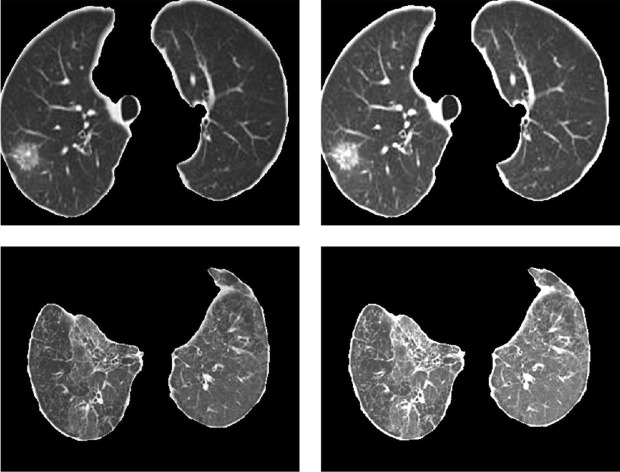

where and represent the average brightness of the COVID-19 region before and after equalization, respectively. The corresponding enhancement results are shown in Fig. 7 .

Fig. 7.

Results of adaptive local COVID-19 region enhancement. (Each row corresponds to a group of images. The first and second columns represent the images before and after enhancement, respectively).

The proposed adaptive enhancement algorithm converts the COVID-19 region into an output with the same number of pixels at each gray level, which can effectively improve the dynamic range of pixel gray value by balancing the gray level distribution in the COVID-19 region. Besides, it can make the difference between the COVID-19 region and the normal region larger, as shown in Fig. 8 .

Fig. 8.

Results of adaptive enhancement algorithm (Red regions indicate the lesion before and after the enhancement). (a) Before enhancement; (b) After enhancement.